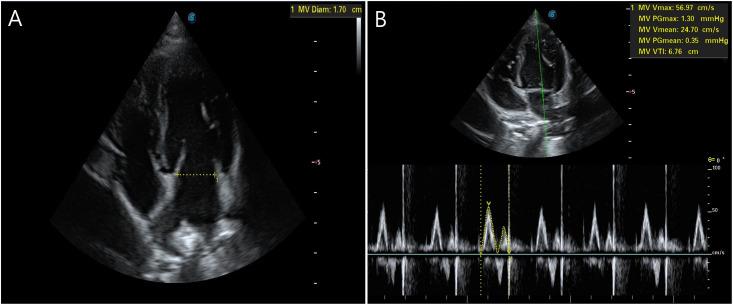

METHODS

The present study used six healthy beagles. All dogs were anesthetized with isoflurane and allowed to breathe spontaneously in dorsal recumbency. After instrumentation, LC was performed at four different pressures in a sequential, non-randomized manner: (1) 10 mmHg, approximately half of the minimum value within the range; (2) 22 mmHg, a commonly used pressure within the range; (3) 44 mmHg, twice the pressure of the minimum value within the range; and (4) 60 mmHg, twice the pressure of the maximum value within the range. At each pressure, CO via transthoracic echocardiography, IAP, and cardiorespiratory parameters were measured before, during, and after LC.

本研究使用了6只健康的比格犬。所有犬只均用异氟醚麻醉,并使其在背卧位自主呼吸。仪器安装后,以非随机顺序在四个不同压力下进行LC:(1)10 mmHg,约为该范围内最小值的一半;(2)22 mmHg,该范围内常用的压力;(3)44 mmHg,该范围内最小值压力的两倍;(4)60 mmHg,该范围内最大值压力的两倍。在每个压力下,在LC之前、期间和之后测量经胸超声心动图测得的CO、IAP和心肺参数。